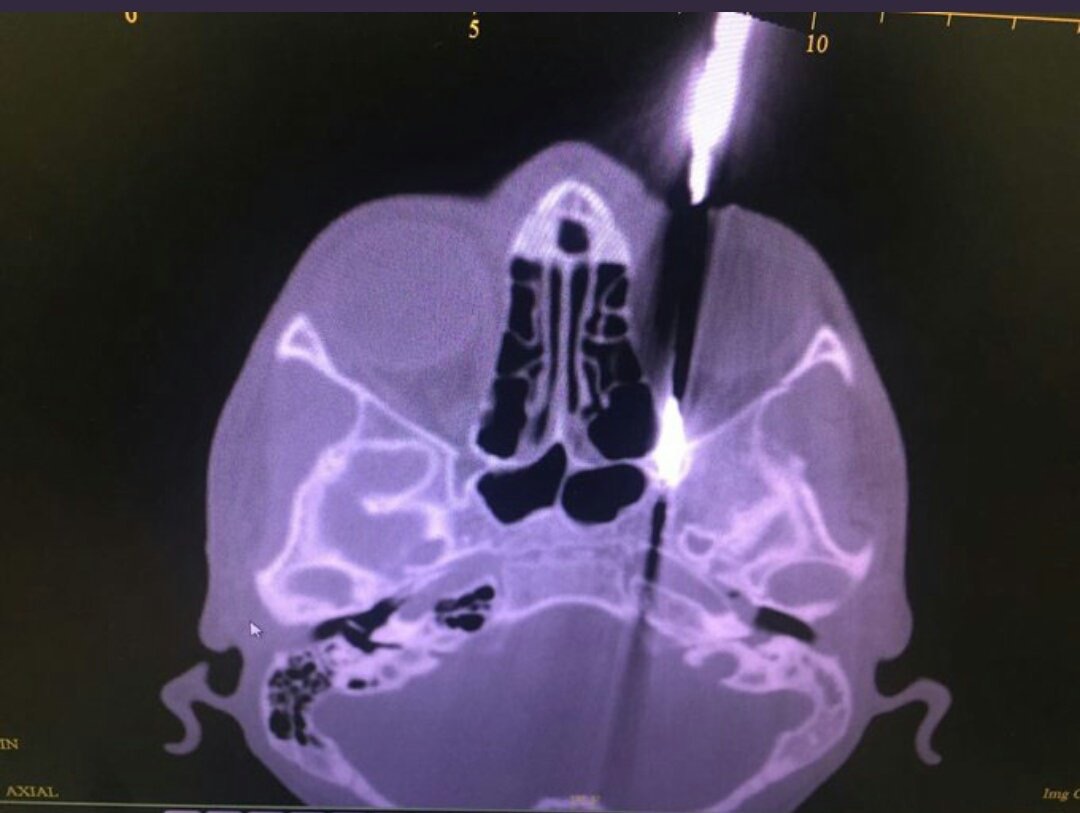

تمكن أطباء من مستشفى خولة في استخراج “عمود معدني” عالق في منطقة حرجة داخلة الجمجمة لمراهق يبلغ من العمر 14 سنة.

وذكرت صحيفة “الوطن” أن الدكتور تيمور البلوشي قال أن هذه العملية تعد الأولى من نوعها في السلطنة، حيث مر العمود من خلال تجويف الجمجمة الذي يحتوي العين متفاديا اياها.

ويذكر ان المريض قد عاد الى البيت بعد 4 ايام قضاها في المستشفى وهو بصحة جيدة و دون تأثر النظر.